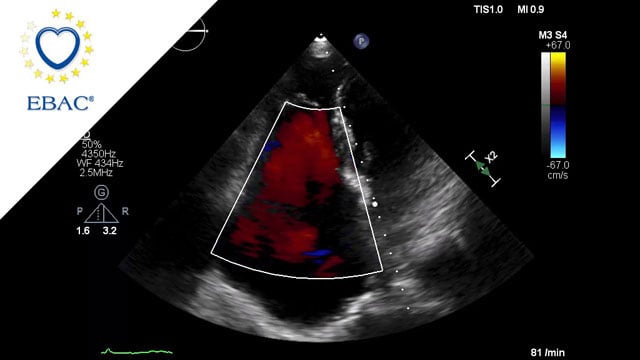

Severe MR in a high-risk patient with a suboptimal anatomy for M-TEER: what other options can we find?

Multimodality imaging reveals fibro-calcific leaflet disease, restricted motion, and a short posterior leaflet, making him a suboptimal candidate for M-TEER and prompting consideration of transcatheter mitral valve replacement. How would you treat?